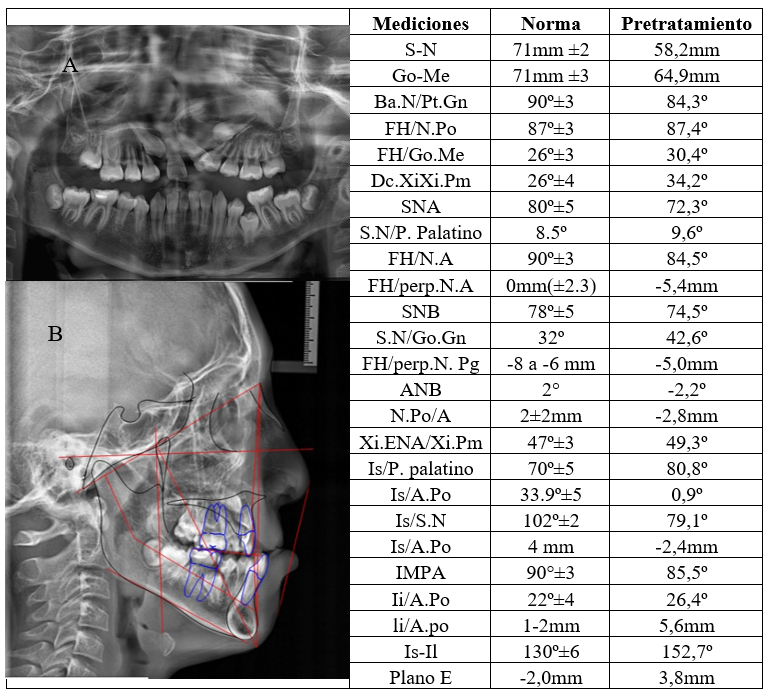

La radiografía panorámica mostró una fisura en el nasoalveolo palatina izquierda, agenesia de las piezas 1.2 y 2.2, retención de las piezas 1.3, 2.3 y 3.5; además de la existencia de gérmenes de los terceros molares superiores e inferiores. El análisis de cefalometría mediante programa Dolphin v.11.0 confirmó la presencia de un biotipo dolicofacial y de maloclusión de clase III esqueletal, causada por la retrusión maxilar, retroinclinación y retrusión del incisivo superior; así como, protrusión del incisivo inferior (figura 2).

Fuente: historia clínica del paciente.

El análisis cefalométrico digital postratamiento reveló cambios esqueléticos favorables: aumento de 4,3˚ en el ángulo SNA, indicando una protrusión del maxilar; mientras que, la medida de SNB mantuvo el valor inicial, pero la maloclusión disminuyó a clase I esqueletal con un biotipo dolicofacial, se observó mayor proinclinación y protrusión de los incisivos superiores y presencia de retrusión en los incisivos inferiores (figura 6).